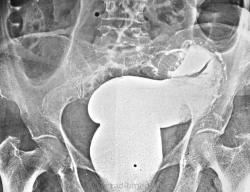

Пытались уточнить природу непроходимости. В ургентном порядке ирригоскопия.

Опухоль ректосигмойдного отдела, раковый канал.

Для ракового канала слишком ровные контры, слишком симметрично, слишком длинно...все таки - инвагинация.

Чекто видно дефект напонения. Экзофитная опухоль.

Было дано заключение о наличии стенозирующей опухоли в сигме, что и подтвердилось на операции.

Если проследить правый контур образования - видно что он уходит ниже кости..., вероятно это контур раздутой сигмы проксимальнее сужения. У пациентки классика системного остеопороза.

По мне так это просто пестрят костные балки, ну и конечно остеопроз. Таз женский